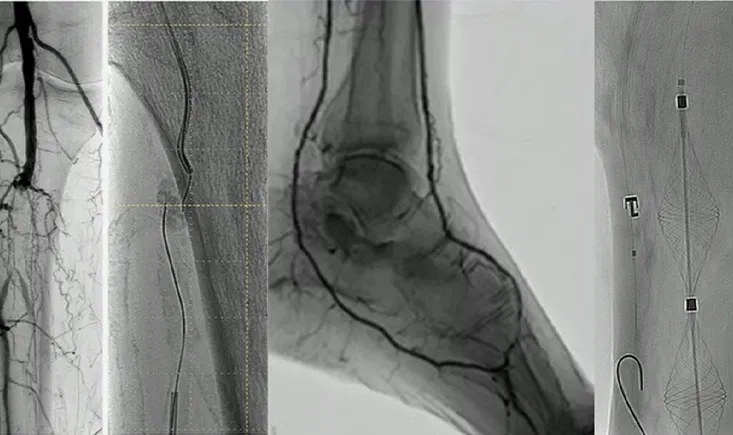

This PVI 2024 session explores the CLI Global Society’s mission and showcases strategies like bridging procedures, profunda femoris revascularisation, and deep venous arterialisation, from both surgical and endovascular perspectives.

In this PVI 2024 session on peripheral arterial disease (PAD), explore the latest tools and technologies shaping treatment. The session highlights survey results on SFA/popliteal lesions, insights on bioresorbable drug-eluting scaffolds, advances in perfusion assessment with hyperpectral imaging, and the role of percutaneous transmural arterial bypass for complex lesions. Experts also discuss which imaging devices—angiography, IVUS, EVUS, or CO₂—most effectively improve patient outcomes. The session provides practical guidance on current strategies and emerging technologies, helping clinicians stay up to date and make informed treatment decisions.

In this brief interview from PVI Course 2024, Andrej Schmidt discusses two innovative approaches in vascular surgery. First, he highlights a bioresorbable scaffold study, which shows promising results in improving patency and reducing re-interventions for frail patients with critical limb ischemia below the knee, while noting its limitations in treating long, calcified, or very distal lesions. He also delves into the encouraging early outcomes of a totally percutaneous bypass technique, offering a simplified method for addressing complex femoropopliteal lesions, including chronic total occlusions and restenoses.